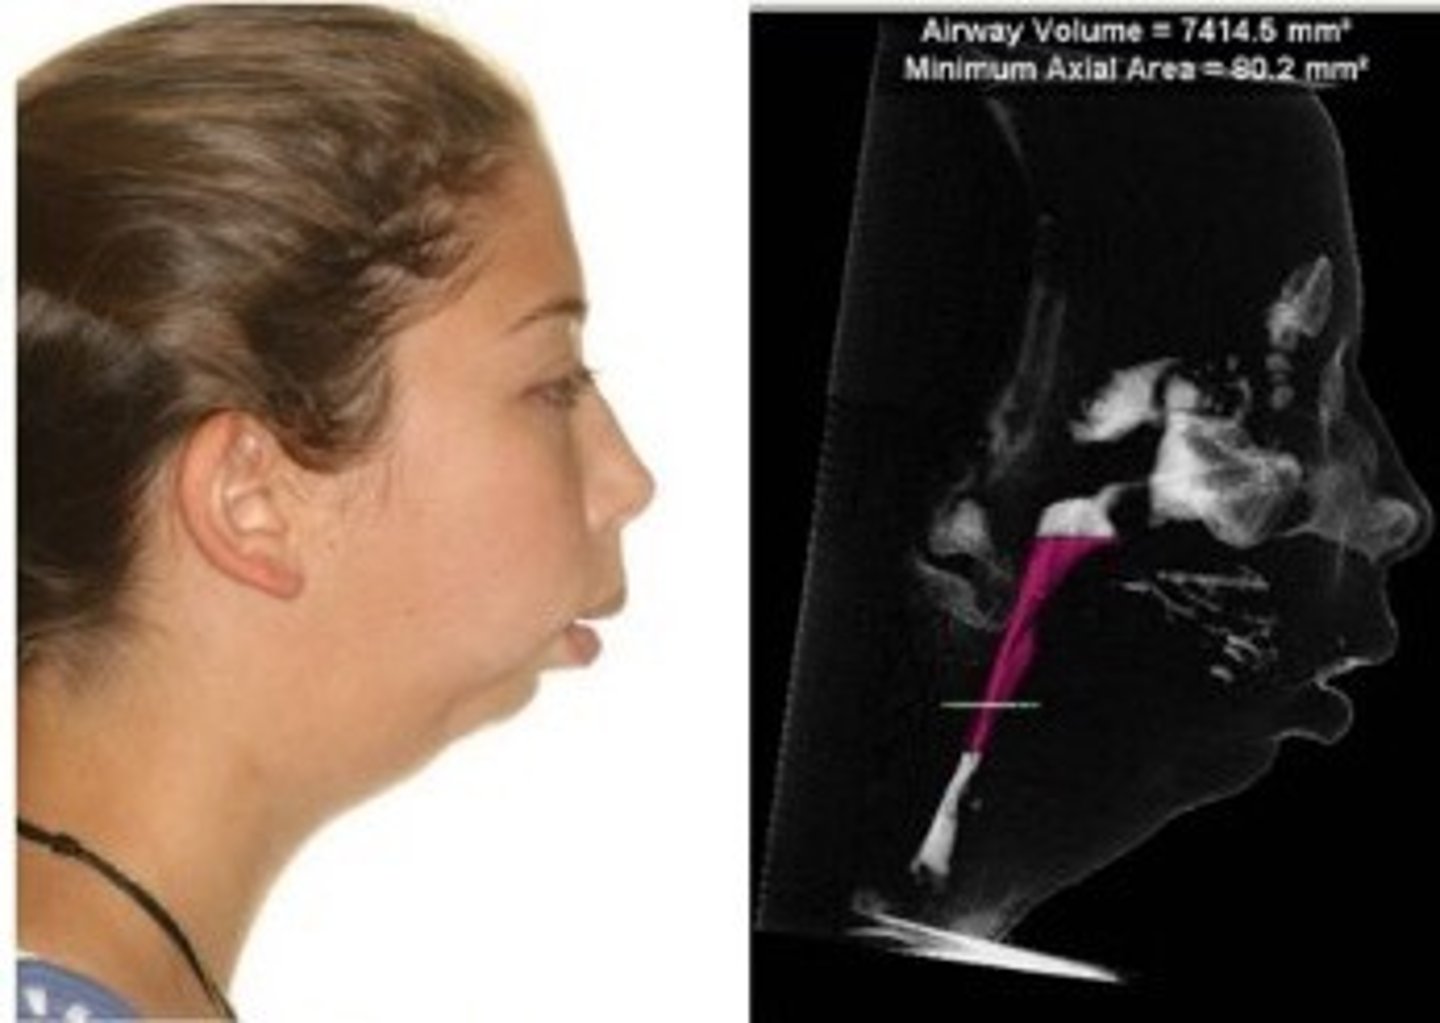

What is micrognathia and retrognathia?

Small chin and no room for tongue